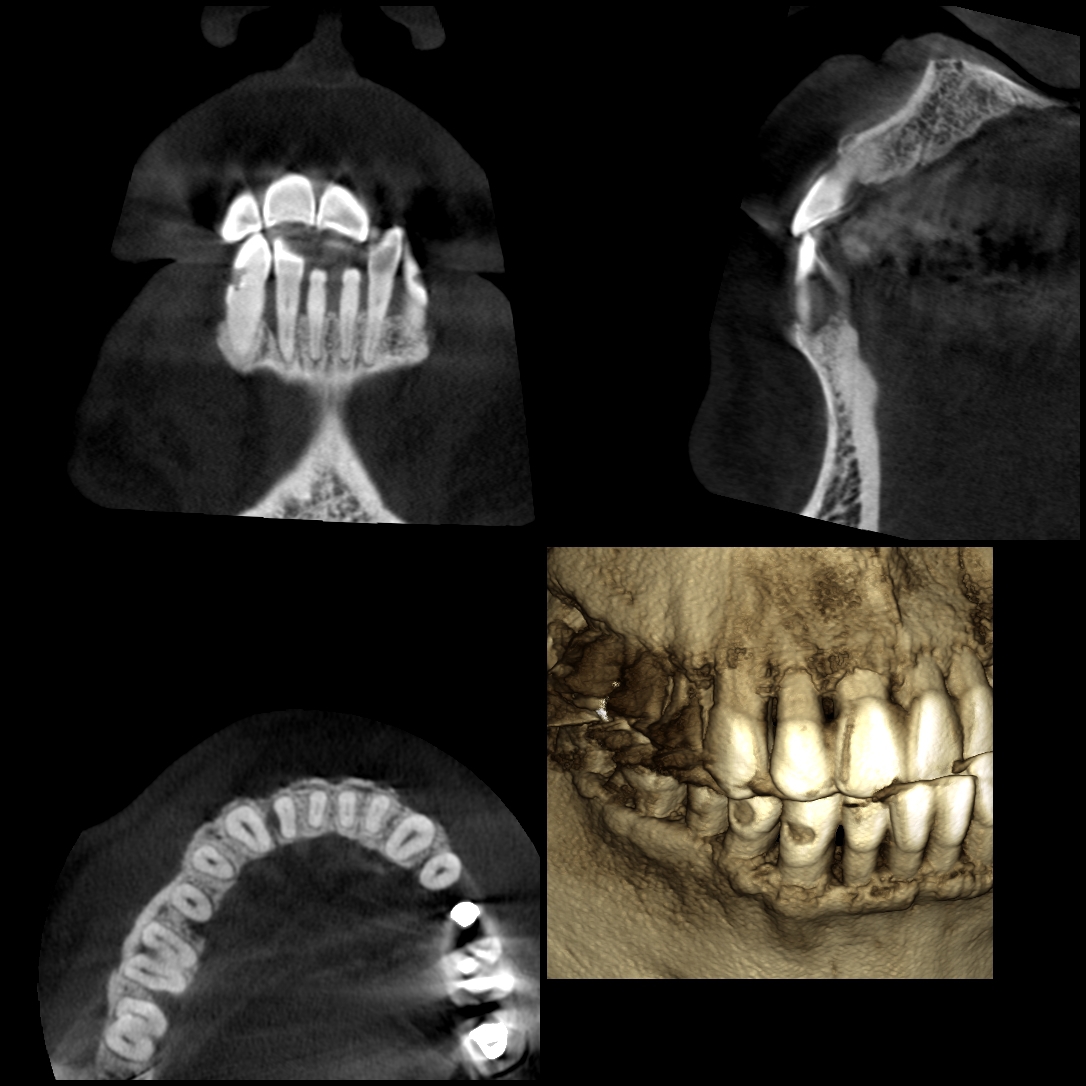

歯周病治療とCT

歯周病が進行すると歯を支えている骨が溶けてしまいます。歯石を取る歯周基本治療や手術を行う歯周外科処置を行う上で、CT撮影により顎骨の形態を三次元的に把握することは非常に有益です。特に中等度から重度の歯周病患者さんの場合には、治療のアプローチを考える上でとても役立ちます。